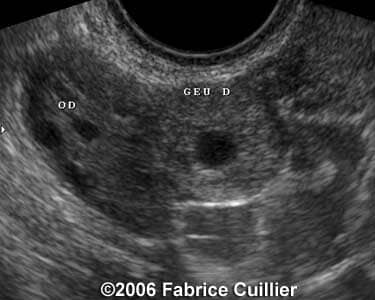

Case 4

case4a

case4b